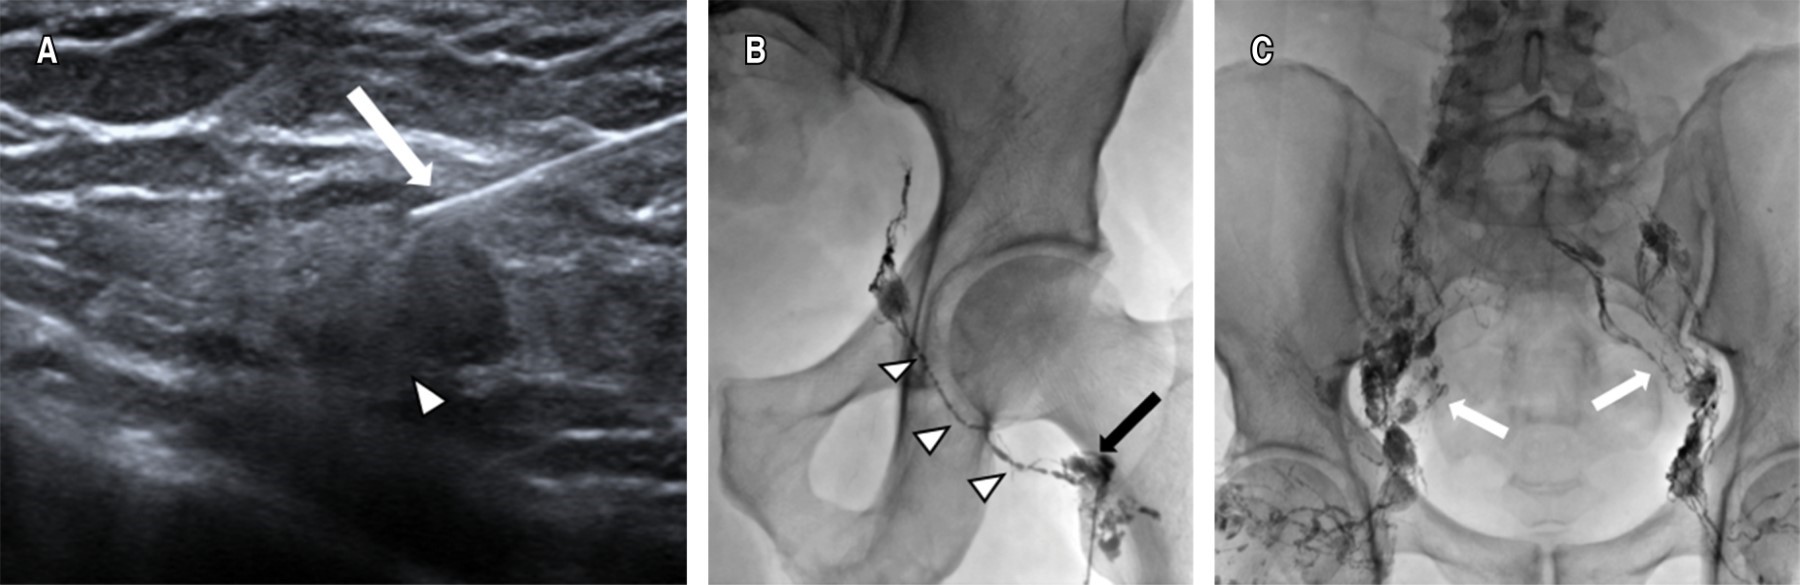

Intranodal lymphangiography

The largest bilateral inguinal nodes distal to the inguinal region were identified under ultrasonographic guidance; Lipiodol® was then injected using a 22 G needle, the tip of the needle being placed in the transition zone between the cortex and hilum of the lymph node. A slow manual injection of Lipiodol® was performed and observed under fluoroscopic guidance in order to confirm the correct position of the needle. A total volume of 10 to 20 mL of Lipiodol® was injected. Images were obtained under fluoroscopic control every five to 10 minutes during the course of the Lipiodol® injection to observe progression through the pelvic and abdominal lymphatic ducts (Figure 1).

Intranodal LG is considered technically satisfactory if the target lymph node is successfully selected and the lymphatic channels of interest, including the chyle cistern, are adequately visualized with Lipiodol®.